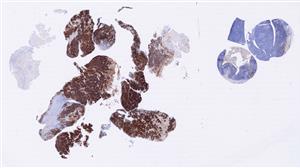

背部皮下肿物 |

男, 65岁, 因“发现背部皮下肿物1月余”入院。患者1月前无明确诱因出现背... |

上海市同济医院 |

有诊断 |